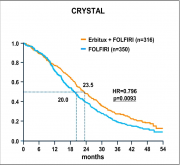

| 15:30, 27 במאי 2013 | CRISTAL1.png (קובץ) |  |

84 קילו־בייטים | Motyk | 1 | |